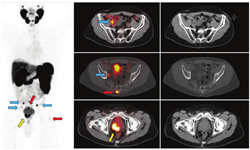

第二,CTVs可以被扩展到包括目前一线影像学未见的疾病区域,并且通常不是一致的CTVs靶点(图3)。第三,转移性疾病的证据表明,单靠局部治疗是无法治愈的。在寡转移性疾病(较低的转移性疾病负荷,在3~5处部位出现不同表达)的背景下,许多医师提供转移导向治疗,旨在局部消融转移灶(图4,图5,图6),转移导向治疗是当前众多临床试验的主题[54]。最后,在某些PET/CT意外显示的弥漫性转移病灶的病例中,放疗可能是无效的。

目前的一线影像学用于指导当前前列腺治疗的许多临床试验。随着PET/CT被纳入常规检查,许多被现有影像学划为N0或M0期的患者很可能被更准确地分期为N1或M1。Roach等[78]最近报道了431例原发和复发前列腺癌患者68Ga-PSMA PET/CT的检查结果,这些患者的一线影像结果呈阴性或不明确。PET显像显示分别有39%和16%患者有先前未知的淋巴结疾病和远处转移病灶[78]。

许多被PET/CT提高了分期级别的患者,转移性疾病的负担有限。对于初始分期有N1影像学证据的患者,目前的治疗方针包括前列腺和盆腔淋巴结放疗及长期雄激素去势治疗[79]。对有N1影像学证据的患者,局部治疗失败后的治疗方法尚不清楚。前列腺癌M1期的患者主要采用雄激素去势治疗。然而,对许多临床医师来说,以不同于全身广泛转移患者的治疗方式来治疗有限的转移病灶(寡转移)患者似乎是合理的(研究者对寡转移前列腺癌有不同的定义,一般指最多有3~5处明显的远处转移)。转移导向治疗,是通过SBRT或转移瘤切除术,伴或不伴有全身系统性治疗的一种正在策划进行中的前瞻性试验策略[80]。前列腺癌寡转移患者是否最终会受益于与全身广泛转移转灶不同的治疗策略目前尚不清楚。不过在任何情况下,随着临床医师采用PET/CT进行初始和复发分期,对这些患者的识别可能会大大增加。